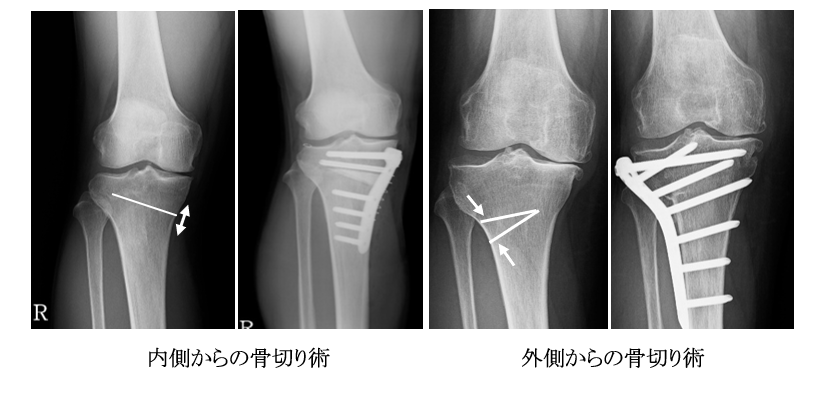

骨切り術は内側から骨切りを行う方法と外側から骨切りを行う方法があります。

内側からの骨切り術では、内側から骨に切り込みを入れて開いて人工骨を挿入してプレートで固定を行います。外側からの骨切り術では腓骨の骨切除を行い、脛骨の外側の骨を楔状に切除してプレートで固定を行います。

O脚の患者さんの多くは内側からの骨切り術で対処できますが、この方法では矯正角度に限界があり、膝の伸ばしにくさが改善しないため、変形の強い患者さんでは外側から骨切りを行っています。